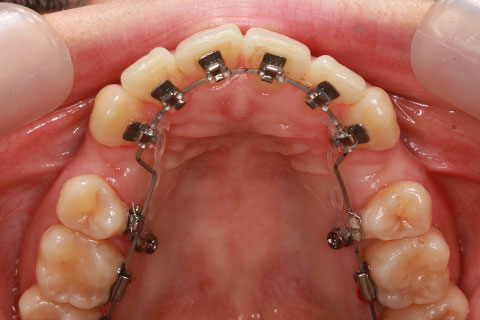

治療後

- 年齢・性別

- 25歳女性

- 治療期間

- 2年0ヶ月

- 抜歯

- 上下4番抜歯

- 治療費

- 110万円

- 治療内容

- 施術の副作用(リスク)

- 表側矯正と比較して、力学的な操作性が複雑なため、ボーイングエフェクトを起こしやすい。